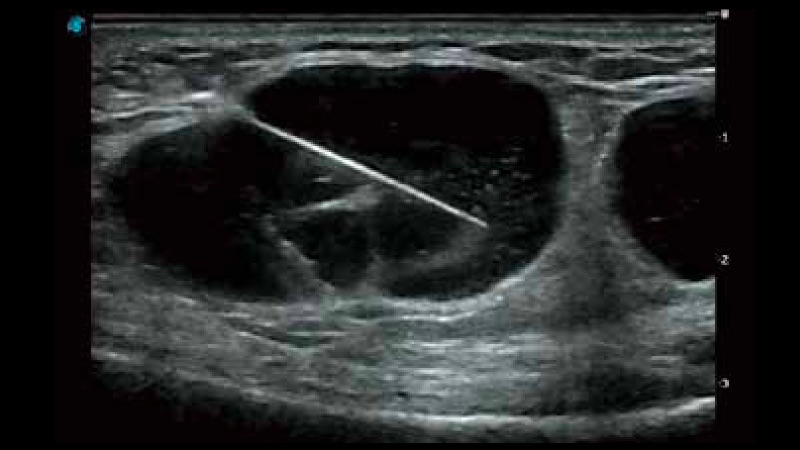

P12 Plus

彩色多普勒超聲診斷系統(tǒng)